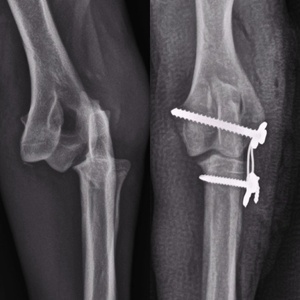

گالری تصاویر